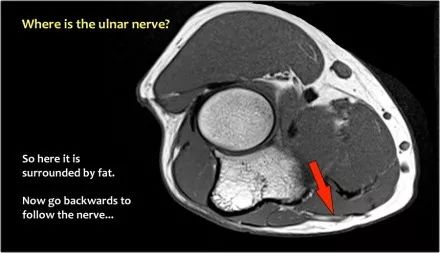

尺神经:在这里,我们看到了肘管内的尺神经。尺骨侧支带的后带形成隧道的底部,而支持带形成屋顶。

该患者有尺神经神经病变。肘管综合征是一种常见的周围神经病变。它产生于肘管内尺神经,其中该神经传递肘管支持带的下方的压缩。

肘管综合征的可能原因● 过度使用● 由于纤维组织中的先天性松弛,尺神经半脱位● 肱骨骨折伴游离体或愈伤组织形成● 由上髁或鹰嘴引起的关节炎● 存在肌肉异常● 软组织肿块:神经节,脂肪瘤,骨软骨瘤,继发于类风湿性关节炎的滑膜炎,感染(例如结核病)和出血。

当他们将尺神经带出隧道时,他们把它放在哪里,它可以是皮下,肌肉下或肌肉内。

因此,当我们回到图像时,您会发现很难找到神经。任何这些皮下结构都可以是转位神经。一种方法是远端跟随结构,直到你发现远端的尺神经位于由脂肪包围的前臂近端的正常位置。然后当你向近端跟随它时,你会发现这是皮下移位。

在这种情况下,有神经炎。神经增大。在T2W图像上有高信号。另一个标志是在矢状图像(箭头)上看到的束的不均匀扩大。